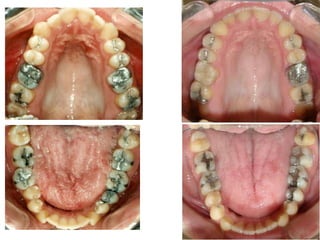

O documento apresenta registros odontológicos de um paciente ao longo de vários anos, incluindo panorâmicas iniciais e subsequentes, remodelações de arcadas dentárias superiores e inferiores ao longo de 7 meses, vedamentos labiais e registros de máxima intercuspidação e guias caninas nas datas listadas.